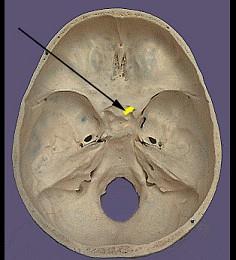

问题 如图箭头所示为哪支脑神经 ( )

选项 A、Ⅳ B、Ⅰ C、Ⅲ D、Ⅴ E、Ⅱ 一、单项选择题

答案 E